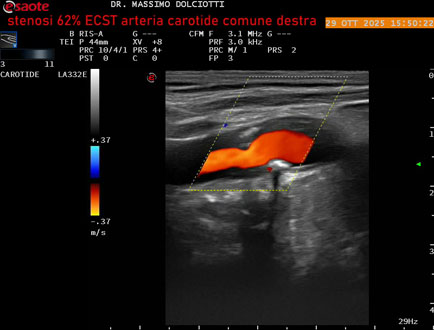

Data inserimento: 30/10/2025

Ecografia del: 29/10/2025

Strumento: Esaote MyLab Eight

Sonda: Lineare Multifrequenza 3-11 MHz

Età Paziente: F 75 anni

Motivazione dell'esame: controllo in pz con ateromasia carotidea ed ipercolesterolemia.

Commento all'esame: le immagini ed il video documentano all'arteria carotide comune destra placca disomogenea tipo 3 della classificazione di Gray Weale, che determina stenosi del 62% calcolato con metodo ECST.

Conclusioni: stenosi del 62% ECST dell'arteria carotide comune destra (62% ECST stenosis of the right common carotid artery).

Presentazione: Dr. Massimo Dolciotti - Ancona

Elaborazione digitale: Andrea Dini - Ancona